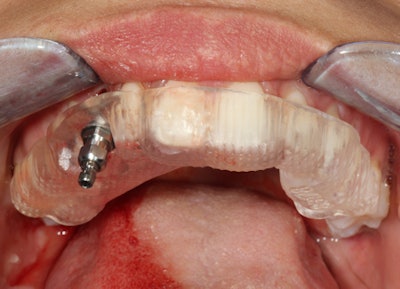

The implant was planned and placed accordingly to be embedded by approximately 2 mm of buccal bone. This should ensure marginal bone stability for long-term success. A resonance frequency analysis with an Osstell device was used to confirm adequate bone-to-implant contact. The implant stability quotient (ISQ) value was 70, which meant that superior initial stability was achieved, verifying objectively that this implant could be loaded.

The patient and I discussed a provisional restoration with a noncontacting fixed tooth before commencing with surgery. A Cerec (Sirona) screw-retained Telio CAD hybrid abutment crown (Ivoclar Vivadent) was fabricated preoperatively and torqued into replace to restore her missing canine. This case illustrates how imaging influenced the clinical decision-making process and provided verification that an immediate implant was indeed possible.